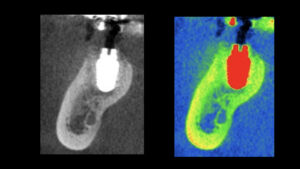

オペから8週でセラミックの歯の型取りをします。炎症を起こして吸収してしまった骨も治癒してきています。